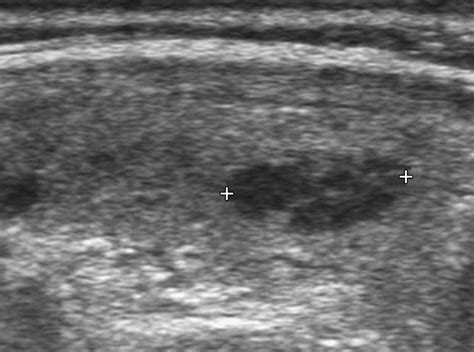

• tiroiditis de hashimoto ecografia

El diagnóstico de la Tiroiditis de Hashimoto se realiza generalmente mediante un análisis de sangre completo. Un nivel elevado de TSH (hormona estimulante de la tiroides) junto con la presencia de anticuerpos anti-tiroideos es el marcador estándar.